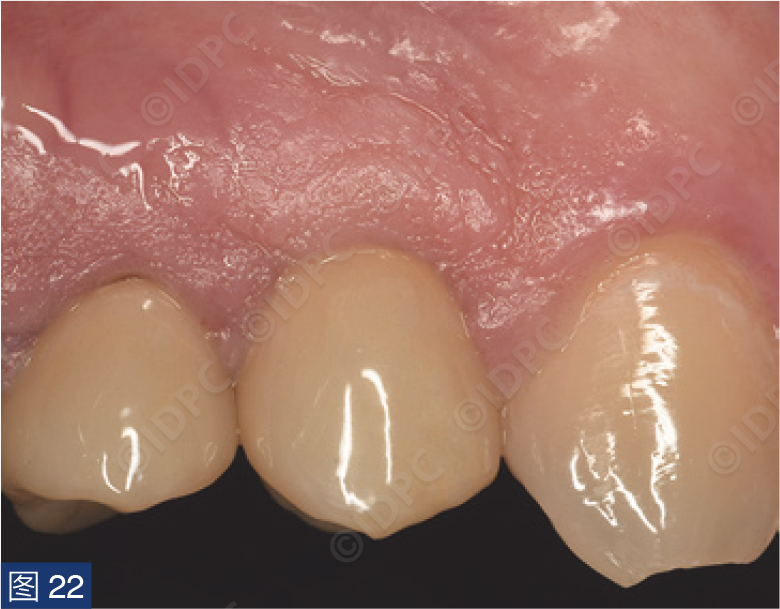

在exocad软件(exocad公司)上进行全数字化修复流程设计,在copaSKY uni.fit钛基底(bredent medical公司)上制作完成螺丝固位氧化锆混合陶瓷一体冠。种植位点显示出足够的颊侧软组织厚度(图12a)及良好的牙龈轮廓(图12b)。取下个性化愈合基台后,种植体周围软组织健康(图13、14),此外,取下后立即进行术前口内扫描以记录软组织轮廓。随后放置扫描体并进行数字印模以记录种植体位置(图15)。同时扫描对颌牙弓及咬合信息。获得的STL文件以数字方式发送至技工室。技工室在钛基底上完成聚甲基丙烯酸甲酯(PMMA)材料的试戴牙冠,以检查邻接和边缘密合情况,同时调整咬合(图16、17)。一旦完成所有调整,进行重新扫描。最终在钛基底上完成螺丝固位的全结构氧化锆混合陶瓷修复体,与牙龈接触的修复体表面高度抛光(图18),并以25 Ncm戴入口内。修复体实现了出色的颜色匹配及临床结果(图19)。螺丝孔用聚四氟乙烯填塞并用树脂材料密封(图20)。术后对照X线片显示修复体正确就位(图21)。六个月复查,增加的软组织轮廓清晰可见,牙槽骨水平保持稳定(图22-24)。

本病例报告展示了一种与植体植入同时进行,且可预测的软组织管理技术。改良的腭侧卷曲瓣技术用于补偿颊侧缺损并获得更好的软组织轮廓。与游离的上皮下结缔组织移植物不同,这种带蒂的方法不仅在血供更好的条件下完成了牙槽嵴的增量,而且还使未覆盖种植体周围的边缘牙龈增厚。将种植体周围粘膜生物转化增厚可以促进种植体周围组织的稳定性。这种方法的另外一方面优势是在愈合阶段没有第二术区或暴露供区,因此不会对患者造成额外疼痛和不适。该技术由于是在种植体植入的同期进行,就避免了第二次软组织增量手术。这也提高了患者的舒适度并创造了积极的牙科体验。种植体植入牙槽嵴顶下方用于补偿经龈愈合期间生物学宽度的扩大。种植修复体周围的牙槽嵴上方的软组织厚度非常重要,因为它直接影响种植体周缘封闭并最终影响治疗的长期成功。破坏种植体周围骨和软组织之间的这种关系可能是早期牙槽嵴骨吸收的原因之一。种植体周围的边缘骨丧失可能会由于骨吸收后出现的牙龈退缩而影响长期的美学效果,这也可能是后期种植体周围感染的最初诱因。与埋入式愈合相比,一期非埋入愈合方案更具可预测性,其优势在于减少了椅旁时间,并且由于没有额外的手术程序,软组织愈合更加成熟。当涉及经龈愈合时,最好使用个性化愈合基台,以便为最终修复获得有利的软组织轮廓。因此,创建一个在牙龈缘水平具有与缺失牙相似尺寸且穿龈部分朝向种植体平台变窄的截面形态,有助于实现这一目标。个性化愈合基台的主要优点是当在无法进行即刻修复时,可以形成与未来修复体穿龈轮廓相适应的牙龈轮廓。综上所述,软组织考量需注意:卷曲瓣、牙槽嵴下植入避免侵犯生物学宽度以及使用个性化愈合基台。选择病例中的种植体系统是因为其独特的骨连接表面。该种植体颈部支持软组织附着,以防止细菌渗透并保护种植体。植体表面的喷砂和蚀刻处理增强了快速骨整合。它具有倒锥设计和双自切压缩螺纹,这对于实现高初期稳定性很重要。此外,copaSKY种植体系统具有平台转移,可以最大限度地减少骨嵴顶的骨丧失,这对于种植体的长期成功和稳定性至关重要。自攻双螺纹设计可实现更快的植入,同时减少热量产生和骨挤压。统计学研究表明,与传统机械加工种植体相比,自切削螺纹的柱形和锥形混合设计、经喷砂和蚀刻表面处理的种植体显示出更高的植入和移除扭矩,同时初级稳定性更佳。最终修复体时按照全数字化流程完成加工制作。口内扫描仪是口腔医学中用于捕获直接光学印模的设备。文献回顾得出结论,目前常用的口内扫描仪提高了时间效率、减少患者不适、消除石膏模型的使用且可以与技师进行更好的沟通。病例选择制作了螺丝固位混合物修复体。一项侧重于螺丝固位或粘接固位冠临床决策的综合回顾显示,螺丝固位修复体具有较少的生物学并发症,并且具有易于拆卸且不会损坏基台和牙冠的优点。与螺丝固位修复体相比,粘接固位冠的移除更具挑战性且更难预测。因此,如果将来出现任何并发症,螺丝固位修复体可以简化病例处置。种植体周围组织中粘接剂的溢出和残留会导致微生物定植及种植体周围组织损伤。使用螺丝固位修复体,更容易评估口腔卫生状态,也更容易执行维护程序。最终修复体选择了抛光处理的全结构氧化锆全冠。在分层氧化锆冠中,饰面瓷在长期磨损后会出现崩瓷或瓷层断裂,从而导致修复失败。一体冠采用CAD/CAM技术制造,抗弯强度及断裂韧性均优于氧化铝基陶瓷冠。